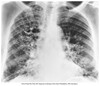

What pathology is seen here?

A

Cystic fibrosis

Lung looks scratchy